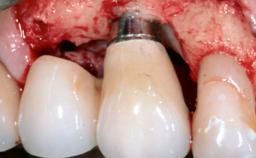

Surgical Management of Peri-Implantitis: Removal of Implant Due to Recurrent Infection Using an Implant-Retrieval Tool

Despite anti-infective surgical treatment, some patients may experience recurrent infection and progressive bone loss requiring additional treatment. This case describes a conservative approach using an implant retrieval tool without the need for excessive bone removal or use of a trephine.